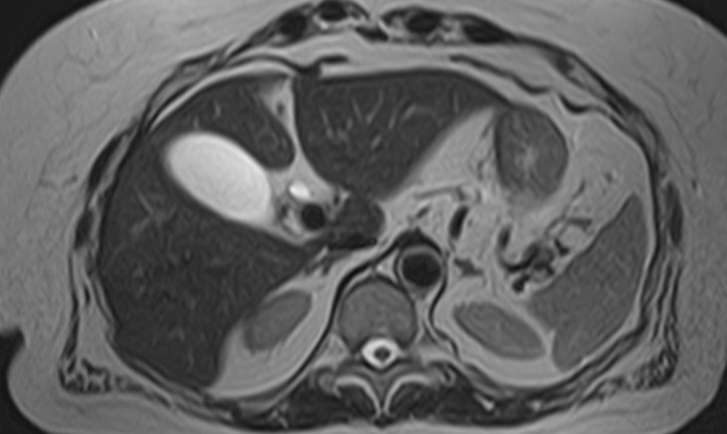

Магнитно-резонансная томография селезенки – высокоинформативный метод исследования органа с использованием внешнего магнитного поля, который позволяет с высокой точностью и достоверностью оценить структуру органа, его размеры, расположение, состояние сосудистой системы и паренхимы селезенки, а также окружающих тканей. МРТ селезенки часто применяется при гематологических заболеваниях, в онкологии, иммунологии.

МРТ селезенки: что показывает

• Новообразования (гемангиомы, саркомы и др.) и метастазы

• Повреждения селезенки (гематомы)

• Сосудистые нарушения (инфаркт, тромбоз вены селезенки, аневризма селезеночной артерии)

• Увеличение селезенки (при портальной гипертензии, болезни Гаучера и т.д.)

• Воспалительные процессы (абсцессы, саркоидоз, гистоплазмоз и др.)

• Кисты селезенки

• Признаки гематологических заболеваний

• Аномалии развития (добавочная селезенка и т.д.)